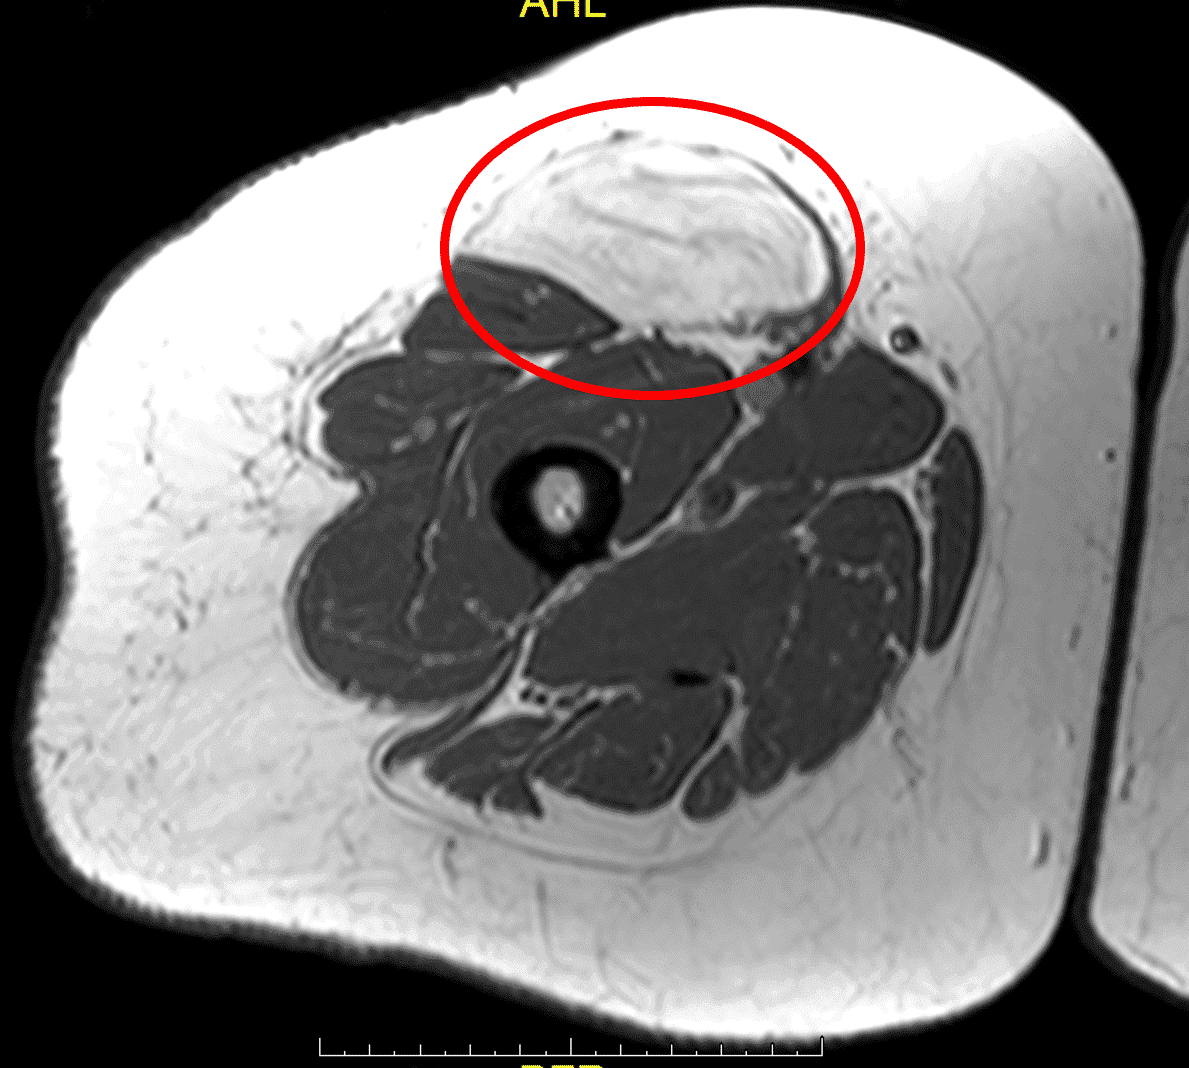

Адекватне обстеження перед будь-яким лікуванням або хірургічним втручанням є надзвичайно важливим. Магнітно-резонансну томографію (МРТ) з контрастом і без контрасту слід розглядати при всіх утвореннях м’яких тканин, які збільшуються або перевищують 4 см. Якщо візуалізація, отримана до направлення, є незадовільною, лікарю слід без вагань повторити або отримати додаткову візуалізацію, щоб адекватно побачити пухлину. В Т1 режимі МРТ якісно візуалізуються доброякісні жирові пухлини, такі як ліпоми або жирові пухлини низького ступеня злоякісності, такі як атипові ліпоматозні пухлини (АЛП), особливо якщо такі пухлини добре окреслені, доволі однорідні та з внутрішнім сигналом, подібним до внутрішнього сигналу від нормальної жирової тканини (зобр. 1).

Зобр. 1: (A) МРТ, фаза T1, що показує доброякісну ліпому правого підгрудного відділу, підтверджену наступною резекцією. Вона за внутрішньою структурою однорідна і з таким самим сигналом, як і від сусідніх жирових тканин.

Зобр. 1: (B) МРТ, фаза Т1, верхня ділянка правого стегна, що демонструє атипову ліпоматозну пухлину, яка дещо більш невиразна з більш складною внутрішньою структурою в порівнянні до навколишньої нормальної жирової тканини.